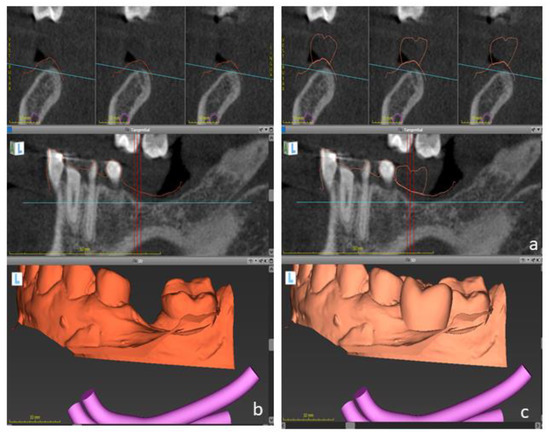

Figure 3.

Digital files were taken to the virtual planning using an implant planning software. DICOM files (a) were matched to dental casts (b) and to the digital wax-up (c) to determine the optimal implant position.

In summary, the “digital imaging and communications in medicine “(DICOM) files were imported to the software, and segmented automatically to comprise the region of interest. Next, “standard tessellation language” (STL) files were imported and superimposed upon DICOM-Data based on common points, which were defined by the user. In addition, the digital wax-up was matched to these files. This approach enabled to plan the implant location, taking into account the bone anatomy and the planned restorations.

Dental implants with appropriate dimensions (size and length) were selected from the library offered by the software to simulate the implant position. In order to avoid inaccuracies caused by dental implants-based artifacts, STL-Data were used as reference to determine the teeth surface. A surgical guide was designed based on the digital planning and printed using a 3D-printer (Formlabs) to guide the surgery.